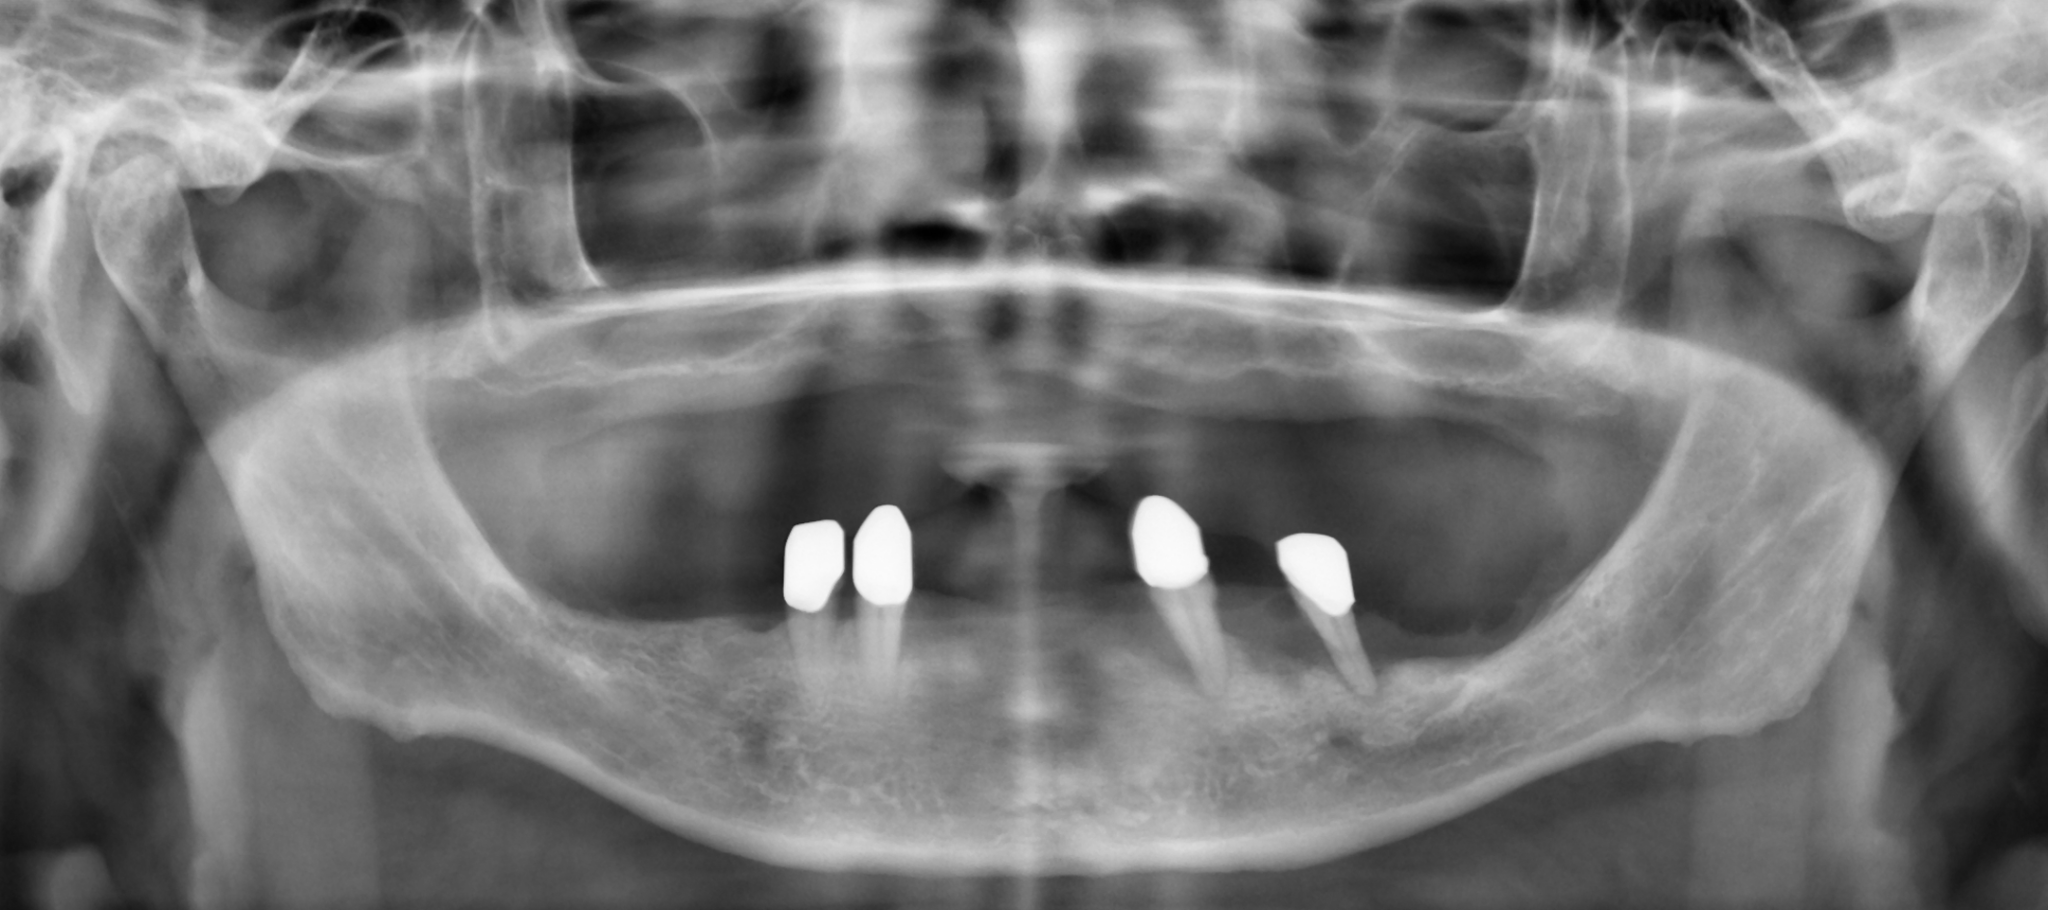

Die Wechselwirkung zwischen zahnmedizinischen Materialien, Behandlungen und der Umwelt sowie deren Einfluss auf die Gesundheit des Menschen steht bei der Umweltzahnmedizin im Fokus. Der Grundsatz dabei ist: Je mehr unterschiedliche Materialien verwendet werden, desto höher steigt das Risiko für Unverträglichkeiten und Komplikationen. Daher haben es sich das Zentrum für Umweltzahnmedizin von Dr. Dr. Michael Rak, Bernried am Starnberger See, und das Labor Highfield.Design, Augsburg, zur Aufgabe gemacht, bei den Behandlungen so wenig unterschiedliche Materialien wie möglich anzuwenden. In diesem Fallbericht wird aufgezeigt, wie eine umfassende Implantatbehandlung bei einem Patienten mit einer nicht mehr passenden Oberkiefertotalprothese und stark geschädigten Pfeilerzähnen im Unterkiefer erfolgreich realisiert wurde.